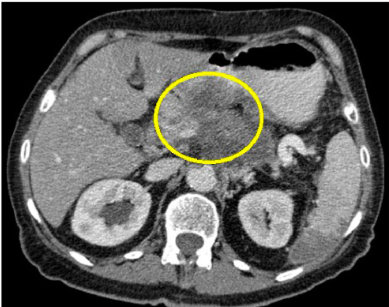

Función de TAC abdominal

• Lesión benigna o maligna dentro de parénquima hepático como quistes hepáticos

• Tumor en páncreas

• Cuando USG no reporta litos pero si hay patron colestásico

• Contrastado para pintar tumor

Quiste

• Epitelio que dentro contiene líquido y benigno cuando está bien delimitado